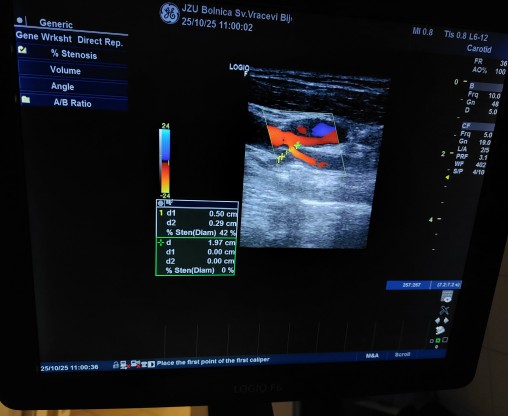

U susret Svjetskom danu moždanog udara, koji se obilježava 29. oktobra, Odjeljenje za neurologiju JZU Bolnica “Sveti Vračevi” Bijeljina organizovalo je u subotu, dodatne kolor dopler ultrazvučne preglede krvnih sudova vrata za 50 pacijenata koji imaju potrebu za ovom dijagnostičkom metodu.

Odjeljenje neurologije raspolaže savremenom dijagnostičkom opremom za EEG, EMNG i kolor dopler ultrazvučne preglede krvnih sudova vrata i mozga, a stručni tim čine iskusni neurolozi i medicinsko osoblje posvećeni stalnom unapređenju dijagnostike, terapije i rehabilitacije pacijenata.